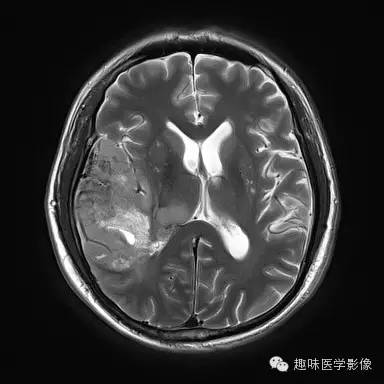

【病例】少突胶质细胞瘤1例MR影像表现

性别:男年龄:48岁 间断性四肢抽搐9月余,头晕伴肢体无力1月余

[影像表现]

右侧颞顶叶、丘脑可见大片不规则异常信号灶,局部脑回肿胀,大小约45×75mm,T1WI呈混杂低信号,内可见多发条状高信号,中央可见更低信号灶,T2WI/FLAIR呈混杂稍高信号,内可见点状低信号,DWI呈混杂高信号,未见明显占位效应,增强后呈多发不规则花环状明显强化灶,内可见多发点状小血管影。

少突胶质细胞瘤,WHOⅡ级。

少突胶质细胞瘤为分化良好、生长缓慢但呈浸润性的肿瘤,典型者累及皮层和皮层下白质,20%-50%有侵袭性(间变性少突胶质瘤)。最佳诊断征象:部分钙化 中年人的皮层肿块,可以侵蚀并使颅骨膨胀。CT平扫为低/等密度,大部分钙化,可有出血和囊变,增强CT表现多样,从无增强到明显增强。MRI常不均匀,T1WI上相对于皮层为低/等信号,T2WI为高信号;除间变外,出血、坏死少见,边界清楚,伴轻微水肿,50%强化。